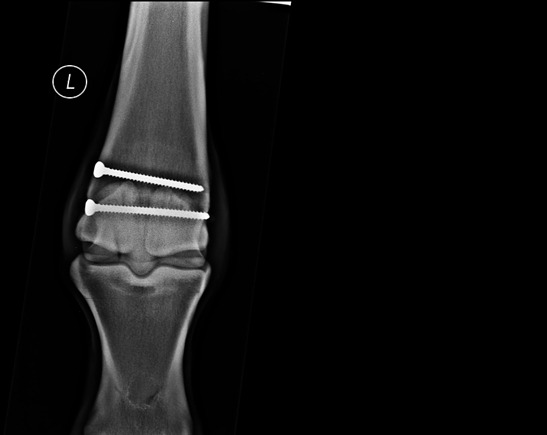

This is a mechanical form of laminitis that occurs when a horse bears excessive weight on one leg for a prolonged period, usually because the opposite leg is severely injured or unusable. This could be because of a fracture, a severe tendon/ligament injury, a nasty wound, a prolonged foot abscess or even (ironically) laminitis. It is well established that this type of laminitis is a risk when treating a broken bone, for example, and sometimes horses are even placed in slings to take some of their body weight, albeit this can lead to other issues, such as rubs, despite careful management.